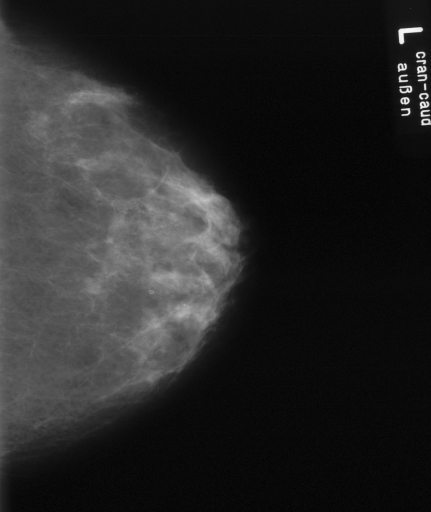

In this series of experiments, we randomly selected three categories from IRMA dataset (namely, breast, foot and lung), and for each category we choose 5 random images from that class (Figures 5, 6 and 7 show these images). When we find “4 out of 180” (4/180) and “8 out of 180” (8/180) projections via micro-DE (tasks that cannot be performed via brute-force), then the question is what can we say about the reconstruction error, in terms of correlation between original and reconstructed images, when we compare evolutionary approximation with the case that we can manage via exhaustive search, namely “4 out of 16” (4/16)? Can micro-DE reach at least the same correlation (similarity) as the brute-force case in lower dimensions? If yes, we may have more confidence in using micro-DE in practice where we cannot apply brute force for benchmarking or direct use, especially for higher dimensions (i.e., the number of projections).

For finding optimal projections based on micro-DE (4 out of 180), we set the parameters of micro-DE to be NFC, , , , and we run each experiment 30 times. For optimal projections based on micro-DE (8 out of 180), we set NFC, , , , and we run each experiment 30 times. The results are presented in Tables 2, 3 and 4. In all cases, micro-DE (MDE) with 4/180 reaches the same correlations as brute force (BF) for 4/16. Of course, MDE finds different projections as it is searching the entire search space of . However, that the same level of reconstruction accuracy can be achieved establishes the reliability of MDE as a practical solution that may even produce a higher-level of uniqueness for Radon barcodes as 4 projections are selected among all 180 angles (the increased uniqueness needs to be verified by applying the Radon barcodes for image retrieval). On the other hand, MDE for 8/180 clearly increases the correlation with statistical significance. This is very encouraging as we can generate more expressive Radon barcodes using a higher number of projections.